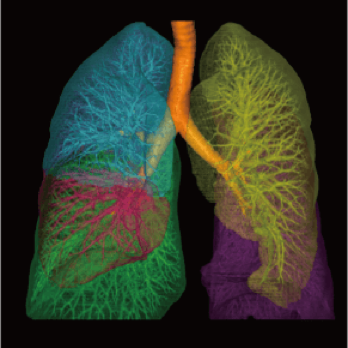

3 core components built on a new industry-leading configuration

Large-capacity tube delivers exceptional stability and durability, ensuring consistently high-quality output even under heavy workloads

High-power generator delivers high mA output for rapid scanning of complex anatomy and large coverage areas, boosting scan speed while enhancing image signal-to-noise ratio and minimizing artifacts

Wide detector expands single-rotation coverage, shortens exam time, reduces motion artifacts, decreases radiation dose, and saves tube exposure time while effectively lowering operating costs